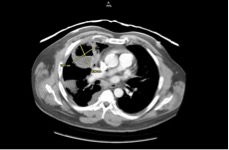

In the ED, the patient had a temperature of 38.9°C and an oxygen saturation of 99%. Laboratory test results revealed an elevated white blood cell count of 12,000/µL with an elevated neutrophil count of 9500/µL. Computed tomography (CT) of the abdomen revealed no stones, but an incidental lung mass was seen. Follow-up chest CT with intravenous (IV) contrast revealed a 6.7 × 7.7-cm cavitary lesion in the right middle lobe with mediastinal adenopathy and right pulmonary embolus (PE) (Figure 1).

Figure 1. CT scans at admission showed a 6.7 × 7.7-cm cavitary lung lesion in the right middle lobe.